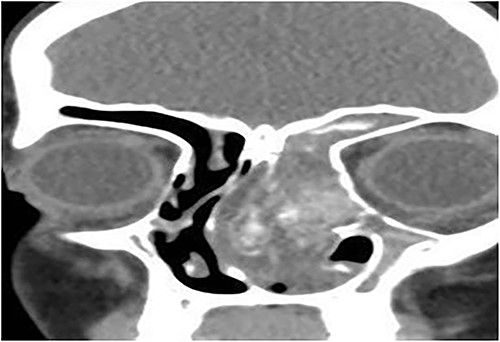

Case 6 (extensive into intraorbital and intracranial structures)

A 15-years-old male presented with bilateral nasal obstruction for a long time associated with nasal discharge, allergic nasal symptoms and headache. Endoscopic nasal examination revealed bilateral extensive nasal polyposis and mucin. CT scan (Fig. 7) and magnetic resonance imaging (MRI) scan (Fig. 8) of the paranasal sinuses confirmed the diagnosis of extensive bilateral allergic fungal pansinusitis with intraorbital and intracranial extradural extension. The patient underwent FESS, and all the polyps, mucin and fungal debris were removed from the sinuses. The patient continued on medical treatment and remained symptoms-free for 5 years follow-up.

Coronal CT paranasal sinuses shows heterogeneous opacities of the ethmoid and maxillary sinuses bilaterally. It is associated with complete opacification and extension through the widened ostiomeatal complex, obliterating the nasal cavities with polyposis. The ethmoid sinuses show expansion with lateral displacement and partial dehiscence of the lamina papyracea bilaterally. The roof of the right ethmoid sinus shows dehiscence with intracranial extension.